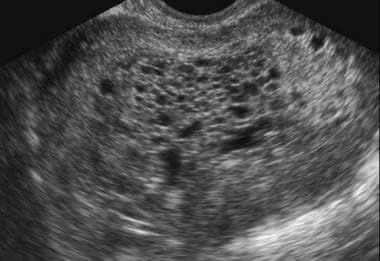

Q.11. What's the finding on USG?

Correct Answer : A

Q.12. What's the finding on USG?

Correct Answer : D

Q.13. What's the finding on USG?

Correct Answer : C